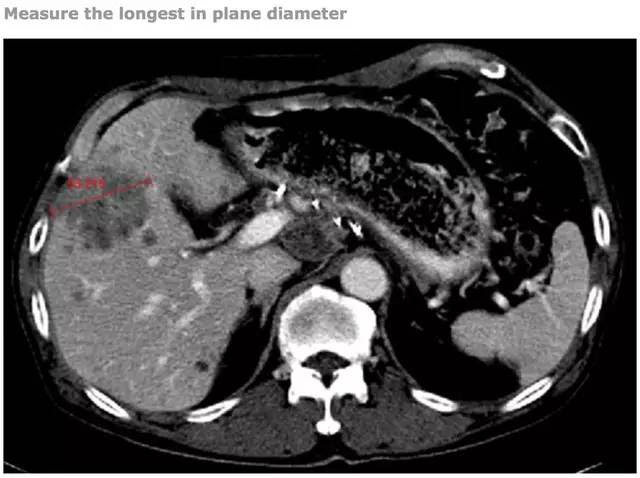

Recist 标准 肿瘤治疗评价的基石